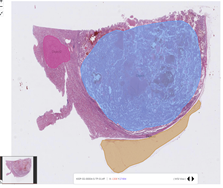

- 원천 데이터 및 Annotaion 라벨 이미지 예시

| 데이터명 | 원천데이터 | Annotation 라벨 이미지 |

| 신장암WSI | ![]() |

|

| 종양 부위와 비종양 영역을 라벨링함 | ||